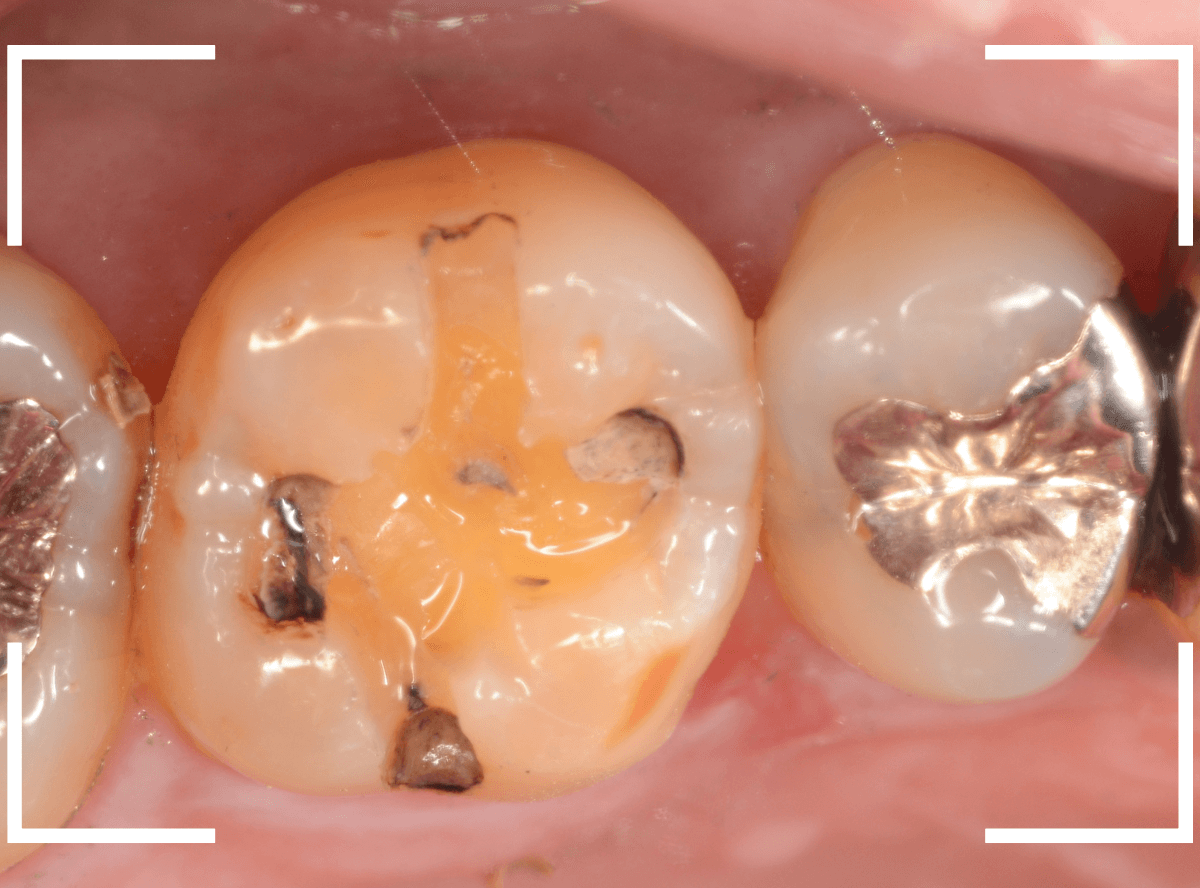

あれ、インレー直下は虫歯がなさそうです。

レントゲン写真を頼りに、歯を削ると、虫歯が出てきました。

大臼歯の虫歯を削っていくと、手前の小臼歯まで虫歯がつながっていました。

やはり、黒い影は虫歯でした。これは深そうです。

メタル・インレーも外して、虫歯を除去します。

全ての虫歯を除去しました。